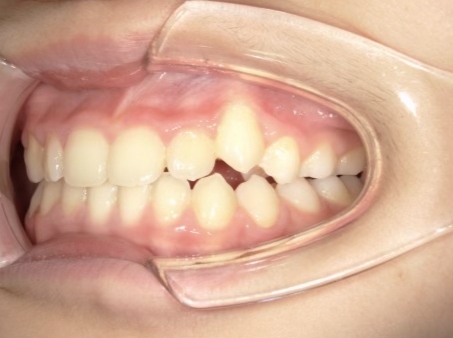

治療中⑤ 小5:10y11m

モノブロック装置継続中、左上3が八重歯で萌出